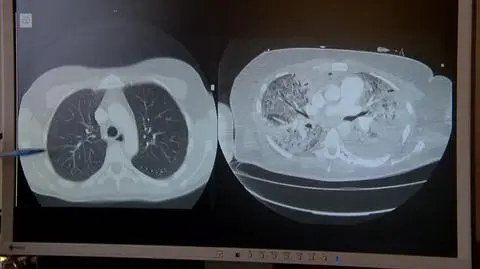

Samo wyjście z COVID-19 to nie wszystko, do pełnej sprawności można dochodzić tygodniami. Koronawirus atakuje wiele narządów, w tym płuca. Bardzo ważna jest rehabilitacja. A żeby dobrze ją przejść, trzeba wiedzieć, jakimi ćwiczeniami można sobie pomóc. Anna Wilczyńska.